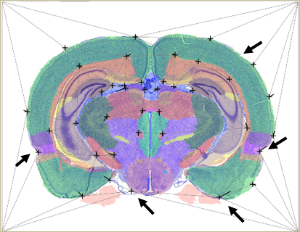

What can I find here?QuickNII_illust.png